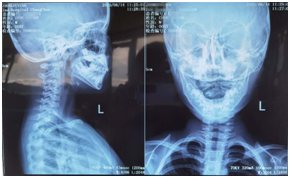

影像:自带当地医院及我院所摄X线片影像均提示寰枢关节半脱位。(左为外院,右为我院)